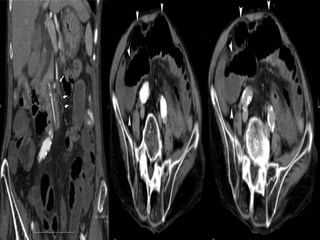

Computed tomography

 Used to for

-screening the patients with suspected

chronic mesenteric ischemia

-Calcified plaque.

-collateral vessels.

CHRONIC MESENTRIC ISCHEMIA

WITH VASCULAR CALCIFICATION

WITH VASCULAR COLLATERALS